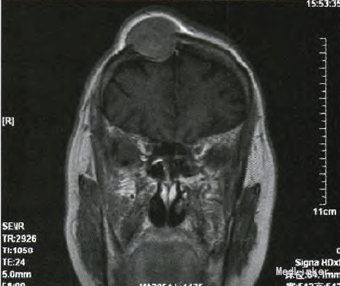

人院行体格检查发现:右侧前额部包块,隆起明显,直径约5cm,形态规则,表面光滑,质软,边界清,无触痛,活动度差,周围可触及动脉搏 动。患者未诉有任何疼痛、瘙痒等不适,追问病史,诉3个月前偶然发现该肿物,生长缓慢。右侧前额部包块超声检查结果见:皮下软组织内可探及范围约2.8cm×2.2cm×3.2cm的低回声包块,侵犯颅骨,形态尚规则,边界尚清,内回声尚均匀,可及动静脉血流信号,可引出动脉频谱,Iu:0.90。考 虑恶性肿瘤转移可能。行头颅MRI增强扫描,提示:右额骨区可见35mmx35ram×37ram大小占位病变,病变破坏颅骨内外板并膨胀性改变,增强扫描 明显强化;余颅内未见明确异常信号,脑室系统及脑沟、脑裂增宽;中线结构无移位,符合恶性肿瘤改变。

据患者病史、查体及辅助检查考虑诊断:①右额骨肿瘤;②甲状腺癌术后肺转移;③高血压病2级中危;④2型糖尿病。完善术前常规检查,行额部开颅右额骨肿瘤切除+硬膜修补术+钛板植入术,术中取部分肿瘤组织送冰冻病理检查示:(右额)纤维结缔组织及骨组织内可见癌浸润,形态符合甲状腺来源。术后肿瘤组织石蜡病理报告为:甲状腺癌颅骨转移,组织形态学符合甲状腺滤泡癌;颅骨四周切缘未见癌。术后行头至腹股沟PET/CT检查:“甲状腺癌术后、I内放疗术后、肺转移瘤粒子植入术后、右额骨转移瘤术后,右额部术后改变,右额部皮质局部葡萄糖代谢弥漫性增高,考虑反应性增生;双肺多发结节,符合转移改变,左下肺内基底段病灶仍有代谢活性;双肺多发陈旧性条索,纵隔及肺门炎性淋巴结;甲状腺术后缺如;左肾囊肿;腹盆部葡萄糖代谢 显像未见异常。